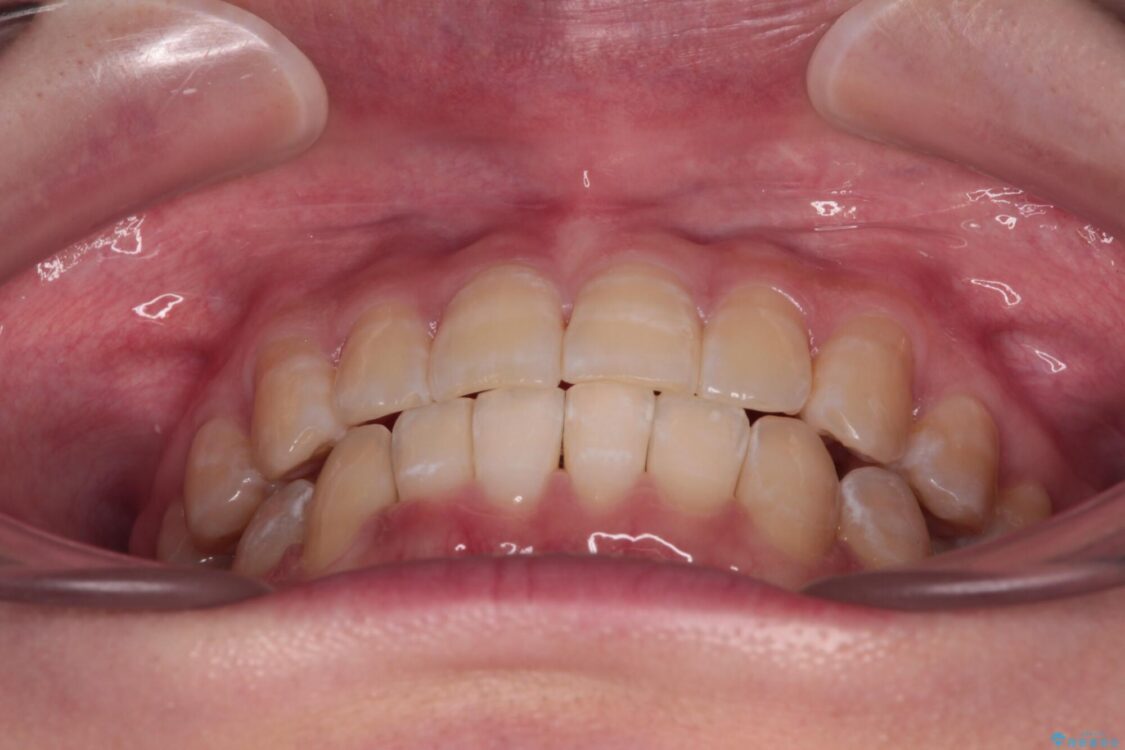

下顎の八重歯を気にして来院された患者様です。

下顎前歯にデコボコが集中していたため、顎間ゴムによる後方移動とIPR(歯と歯の間を削ること)により歯列を整えることとしました。

治療前、下顎前歯のデコボコが集中しており、奥歯の咬み合わせは、上顎に対して下顎が前方位にある状態でした。下顎の歯列を後方へ移動させる治療はインビザラインの得意とするところですので、1年程度で無事に治療を終えることができました。

治療途中

• 【モニター】下顎前歯のデコボコをインビザラインできれいに 治療途中画像